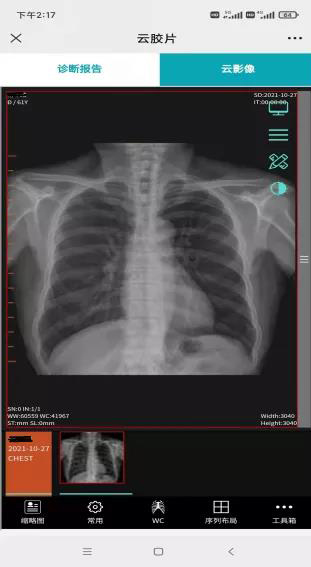

图2 手机上查看检查报告

图3 手机上查看拍片影像